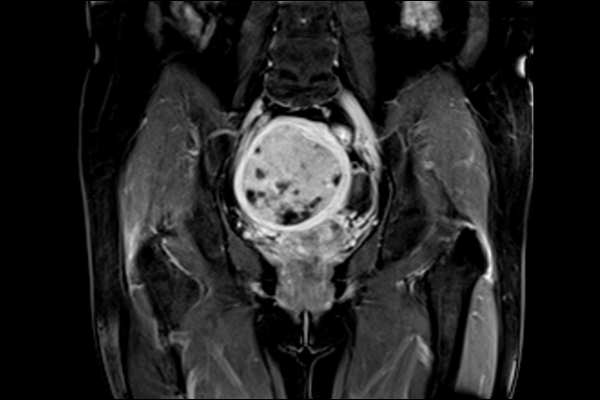

3. Ứng dụng

-

Chụp sọ não và cột sống

Chụp mạch máu (MR Angiography)

Khớp vận động (knee, shoulder, wrist)

Chẩn đoán ung thư (vú, bụng)

Chẩn đoán thần kinh, cơ xương khớp, chấn thương thể thao

Ứng dụng quét nhanh vùng bụng trong nhịp thở ngắn